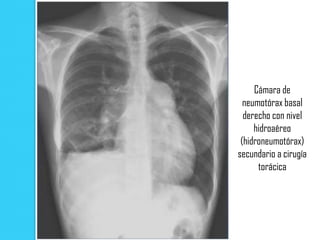

Cámara de

neumotórax basal

derecho con nivel

hidroaéreo

(hidroneumotórax)

secundario a cirugía

torácica

Cámara de neumotórax basal derecho con nivel hidroaéreo (hidroneumotórax) secundario a cirugía torácica